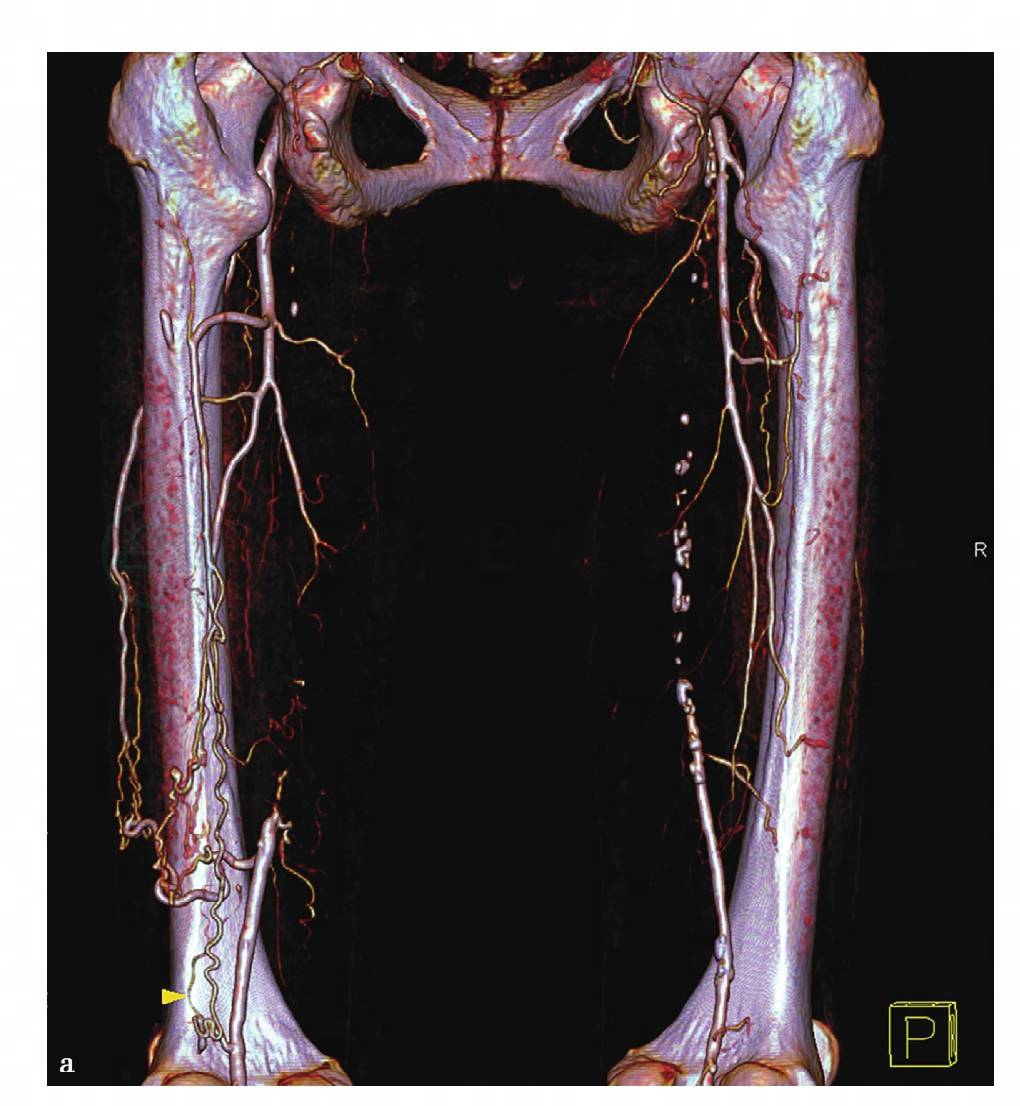

图10 a,双下肢动脉非去骨VR重组图像